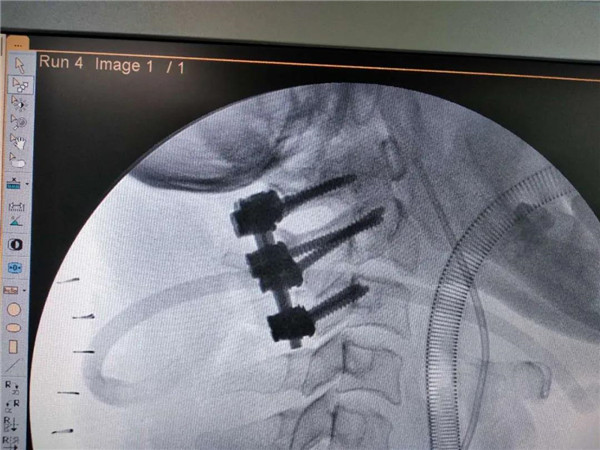

近日,市二医院骨一科为一位患有颈2齿状突骨折的患者,成功实施上颈椎后路手术——颈2齿状突骨折后路切开复位+颈1、2椎弓根内固定+颈3侧块螺钉内固定术。

由于患者上颈椎高度不稳定,患者随时可能有瘫痪、危及生命的风险,入院后科室高度重视,立即组织术前病情讨论,制定手术方案,经颈椎三维CT检查颈1、2椎体无明显变异,颈1椎弓根直径约4mm,刚好可以打入一枚3.5mm椎弓根螺钉,术中不能有丝毫的偏差,否则会造成患者术中大出血,瘫痪甚至危及生命。由吕志华副院长、王小明主任、罗明华副主任医师、杨华主治医师组成的手术团队,在麻醉科、手术室大力配合下,顺利完成手术,整个过程用时90分钟,出血约100毫升。术后患者顺利返回病房,第二天就可坐起。

上颈椎处于颅颈交界区,由于解剖位置特殊,毗邻关系复杂,位置深在,曾被称为手术的禁区。寰椎的椎弓根细小,常会造成置钉困难,稍有偏差,会造成灾难性的后果。相比较传统的枕颈融合术,颈1、2后路椎弓根钉内固定术可以最大限度的保留患者颈椎的活动度,减少对患者以后生活造成的影响。市二医院已成功开展多例该项手术,填补了我市这项技术的空白,标志着医院脊柱外科水平跨上了新台阶,达到了省内先进水平。